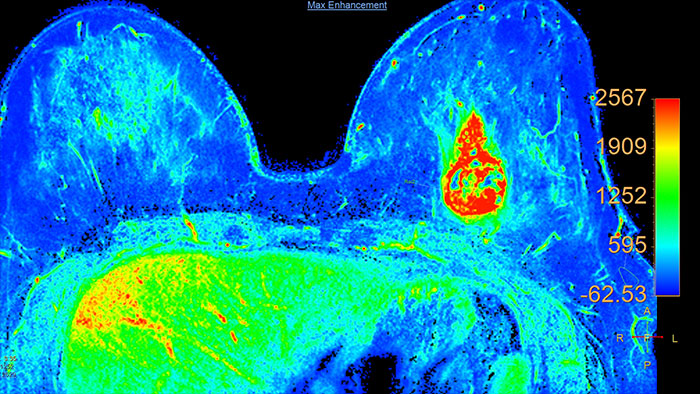

Support in assessing lesions by reviewing blood supply characteristics

Designed to evaluate time intensity curves of a T1 signal enhancement series. The application produces measurements including relative enhancement, maximum enhancement, time to peak (TTP), and wash-in/wash-out rates.

Benefits